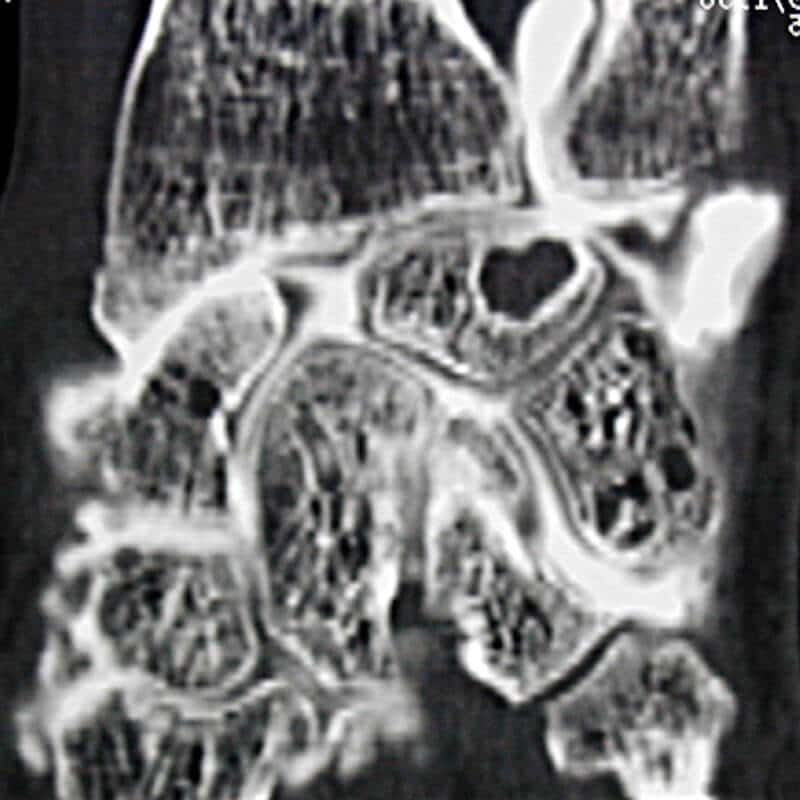

radiographie poignet entorse

Examen radiographique dynamique démasquant l'écart entre scaphoïde et semi lunaire sur les clichés B et C

Cependant, dans la majorité des cas, les radiographies sont normales. Cela ne doit pas empêcher de poursuivre les investigations. L’examen de référence est l’arthroscanner, qui consiste à injecter un produit de contraste dans le poignet avant de réaliser un scanner. Cet examen offre une bonne visualisation des ligaments.